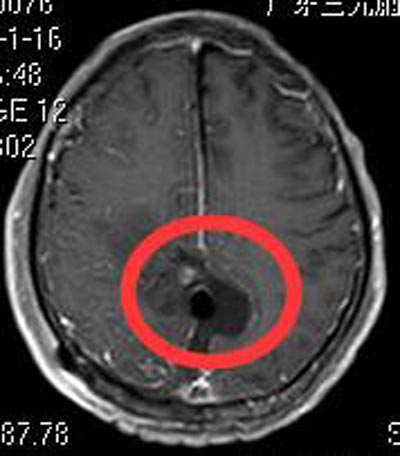

家属要求手术治疗,由鲁明主任主刀,在全麻下行双侧顶部镰窦脑膜瘤切除术,显微镜下见灰白色肿瘤组织,质中,边界较清,与大脑镰粘连紧密,予显微镜下分块切除,保护下矢状窦,全切两侧肿瘤,手术过程顺利。术后刘爷爷四肢肌力正常,康复出院,术后病理结果提示:过渡型脑膜瘤 WHO I级。

刘爷爷术后头痛症状消失,也没有出现瘫痪,一家人非常满意。